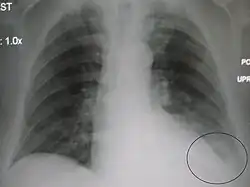

AP CXR showing left lower lobe pneumonia associated with a small left sided pleural effusion -

AP CXR showing right lower lobe pneumonia -

AP CXR showing pneumonia of the lingula of the left lung -

Right upper lobe pneumonia as marked by the circle. -

Left upper lobe pneumonia with a small pleural effusion.

Right lower lobe pneumonia as seen on a lateral CXR